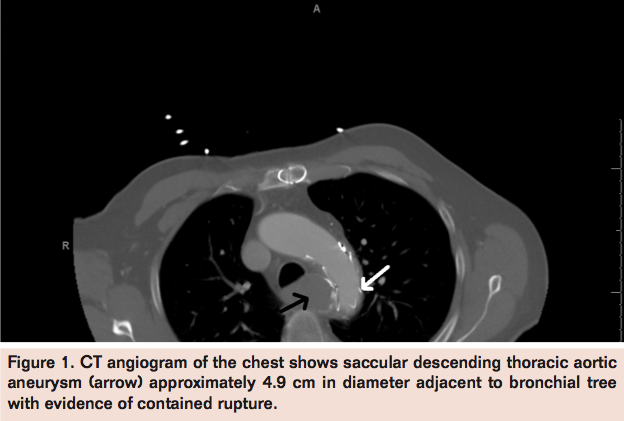

Laboratory studies performed were unremarkable except for hyponatremia with a sodium level of 127 mEq/L. Hemoglobin level was 13 g/dL. Spiral CT angiogram with 3D reconstruction (Figures 1, 2, and 3) revealed saccular descending thoracic aortic aneurysm approximately 4.9 cm in diameter with evidence of contained rupture.